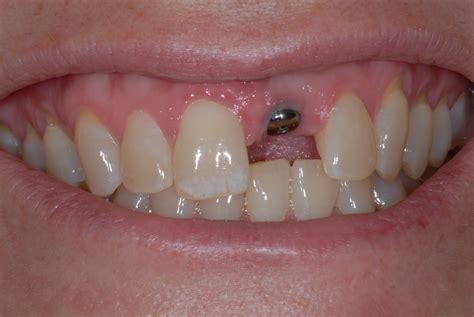

Another common concern is the "temporary" phase. Because the front area is visible, dentists often provide a temporary prosthetic (such as a flipper or a temporary crown) immediately after the surgery. This ensures that you do not have to walk around with a visible gap while the underlying bone and gum tissue heal.

The success of an implant in the front of the mouth often depends on the quality of the surrounding gum tissue. Surgeons pay special attention to the "emergence profile," which is how the crown emerges from the gum line, ensuring it looks identical to a natural tooth rather than a prosthetic attachment.